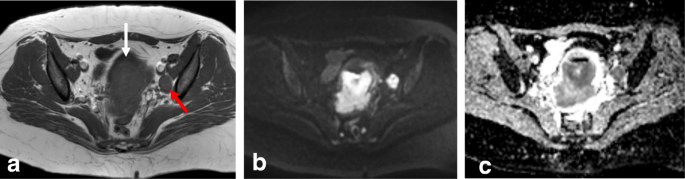

Parametrial invasion (stage IIB)

Tumor extension to the parametrial fat implies disruption of the hypointense cervical stromal rim, with extension of nodular or spiculated soft tissue into the adjacent parametrium (Fig. 14). MRI shows 88–97% accuracy in appropriately evaluating parametrial extension. High-resolution T2WI in the axial oblique plane is essential for assessing the disruption or preservation of the hypointense stromal rim. Preservation of a stromal rim thickness of > 3 mm excludes parametrial involvement (specificity, 96–99%; NPV, 94–100%) [2, 10, 70, 71]. Notably, in patients exhibiting full-thickness cervical stromal replacement by cancerous tissue, diffuse T2 signal inhomogeneity of the cervical rim may be the only feature associated with parametrial invasion. Therefore, accurate exclusion of parametrial involvement requires that the cervical rim be thick (> 3 mm) as well as homogeneous [71].

Tumor visualization with axial oblique T2WI (a), DWI-ADC map (b), and DCE imaging (c) reveals loss of the hypointense cervical rim on the right lateral aspect of the cervix, with an irregular interface between the tumor and the parametrium (arrow). ADC map shows diffusion restriction, and DCE imaging reveals enhancement of the right lateral wall indicating early parametrial invasion (arrows)

Signs of parametrial invasion can also include ancillary findings—such as the presence of an irregular interface between the tumor and parametrium, an asymmetric tumoral bulge, and a peri-uterine vessel encasement in low cervical tumors (Table 6) [2, 10, 70]. Cervical edema and/or inflammation secondary to a recent biopsy, and cervical compression by a large diffuse infiltrating tumor, can be misinterpreted as parametrial invasion, potentially leading to the misdiagnosis of a FIGO IB3 tumor as FIGO IIB. DWI and DCE imaging can help avoid the overestimation of inflammation and improve the accuracy of T2WI for evaluating parametrial invasion (Fig. 15) [2, 10, 68].